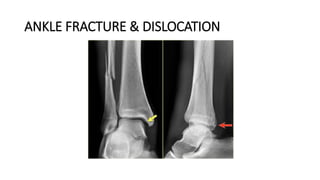

ANKLE FRACTURE & DISLOCATION

DEFINITION

• A broken ankle is also known as an ankle "fracture." This means that one or more of the bones

that make up the ankle joint are broken.

• A fractured ankle can range from a simple break in one bone, which may not stop you from

walking, to several fractures which forces your ankle out of place and may require that you not

put weight on it for a few months.

• Simply put, the more bones that are broken, the more unstable the ankle becomes. There may be

ligaments damaged as well. The ligaments of the ankle hold the ankle bones and joint in position.

• Broken ankles affect people of all ages. During the past 30 to 40 years, doctors have noted an

increase in the number and severity of broken ankles, due in part to an active, older population of

"baby boomers."